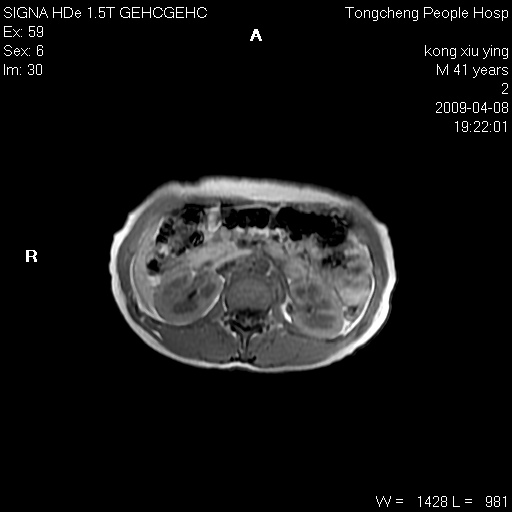

标题: CL1008:【经典】胆囊石榴籽样结石。

女,41岁。健康体检——彩超提示:胆囊显示不清。平素健康,无不适感。

腹部mr扫描及mrcp,图像如下: